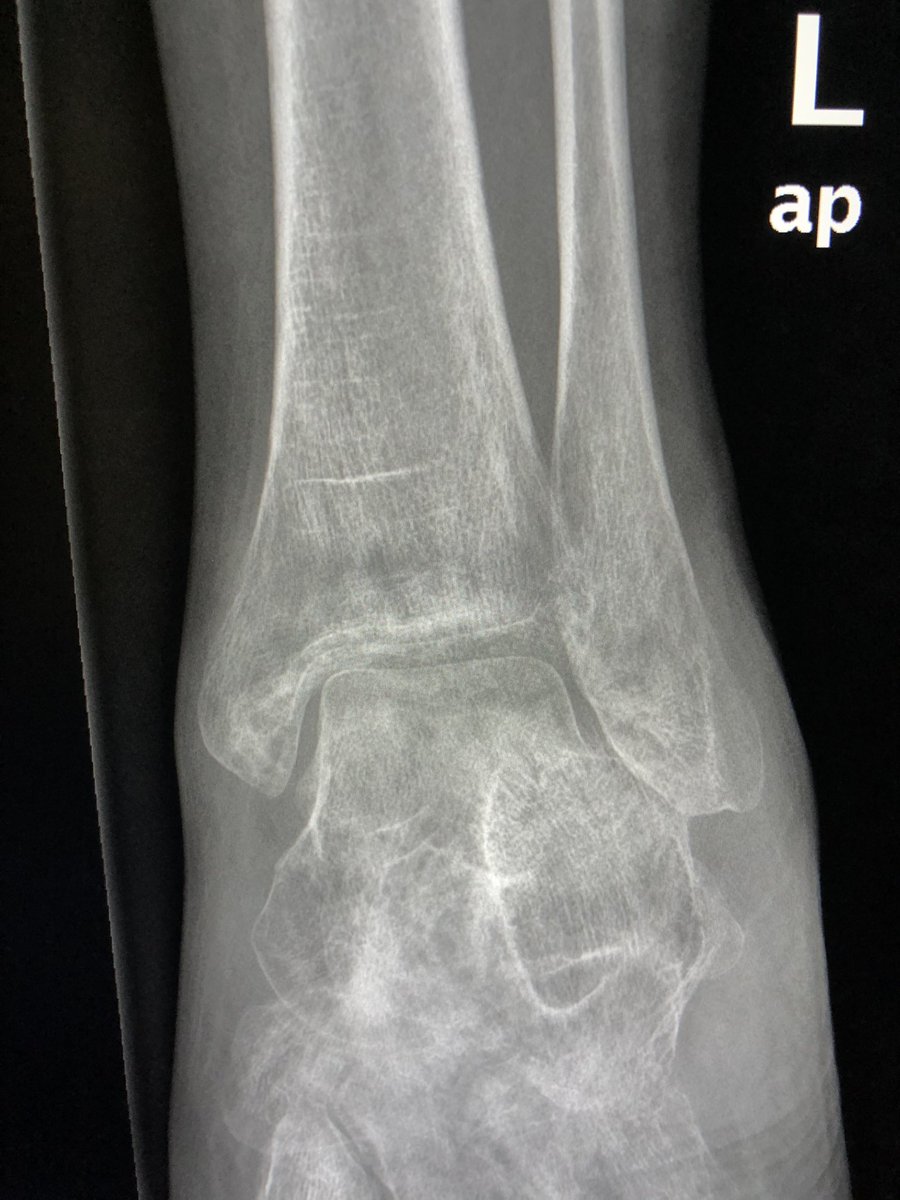

Radiographs may show diffuse regional osteoporosis- as in our case. Subcortical changes may predominate- as in our case (rounded areas of demineralisation disproportionate to the diffuse osteopenia). Trophic changes in soft tissues may be seen.

In the absence of typical clinical syndrome, these findings just represents osteopenia, often disuse.

In severe osteopenia, you will see cortical tunnelling, which is seen in this case!

Talus may start looking like positive Hawkins sign. In fact, one of my residents raised the concern for talus AVN- due to subchondral linear osteopenia, which looks like positive Hawkins sign.